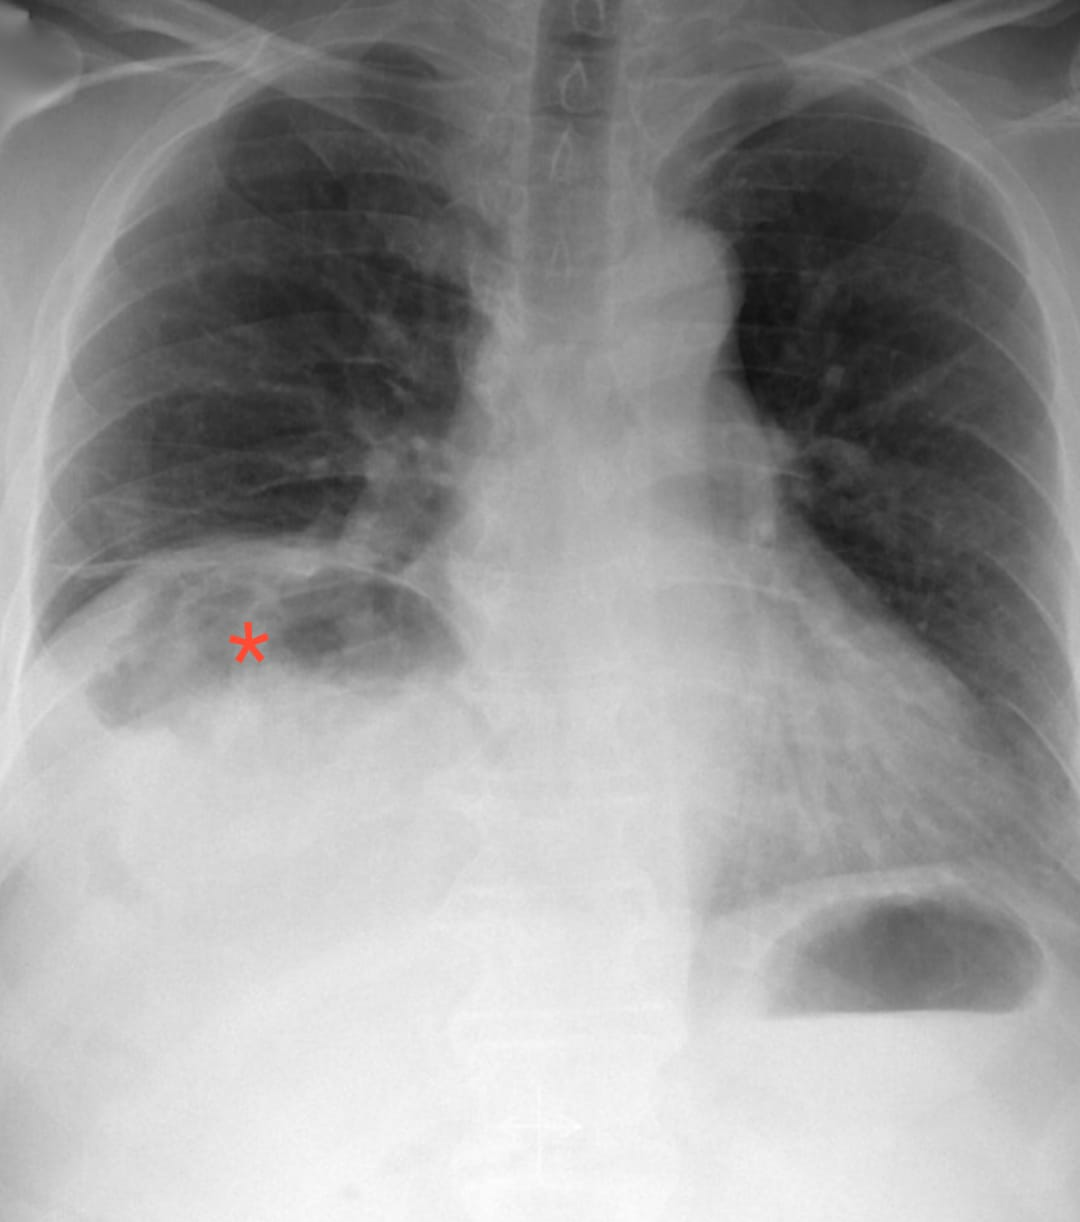

Gas under the right diaphragm Cleveland Clinic Journal of Medicine

Gas under the right diaphragm Cleveland Clinic Journal of Medicine Gas Pain Diaphragm What are the symptoms of trapped gas (gas pain)? here's what causes these signs and symptoms — and how you can minimize them. Passing gas is a typical part of the digestion process. The pain can be sharp enough to send you to the. Most people recognize the telltale signs of. trapped gas can feel like a stabbing. Gas Pain Diaphragm.